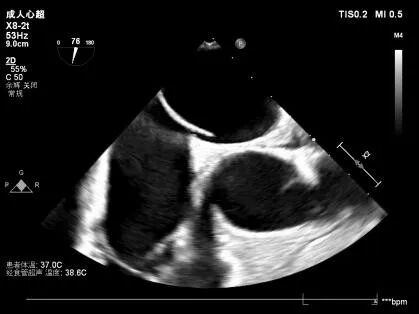

经食道超声心动图通过将超声探头经食道置入,紧贴心脏后方探查,有效避开胸壁与肺部组织干扰,获取更为清晰的心脏深层图像。

其在心脏瓣膜病、心源性卒中、心内血栓、感染性心内膜炎、先天性心脏病等复杂心脏疾病的诊断、评估及介入治疗随访中,具有重要临床价值,已成为提升我院心血管疾病综合诊疗水平的关键技术之一。